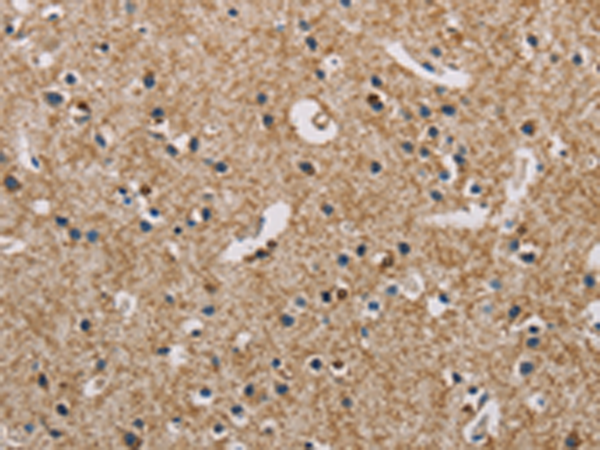

分类: 科研抗体货号: P08003别名: NIP3应用: WB,IHC反应种属: Human, Mouse